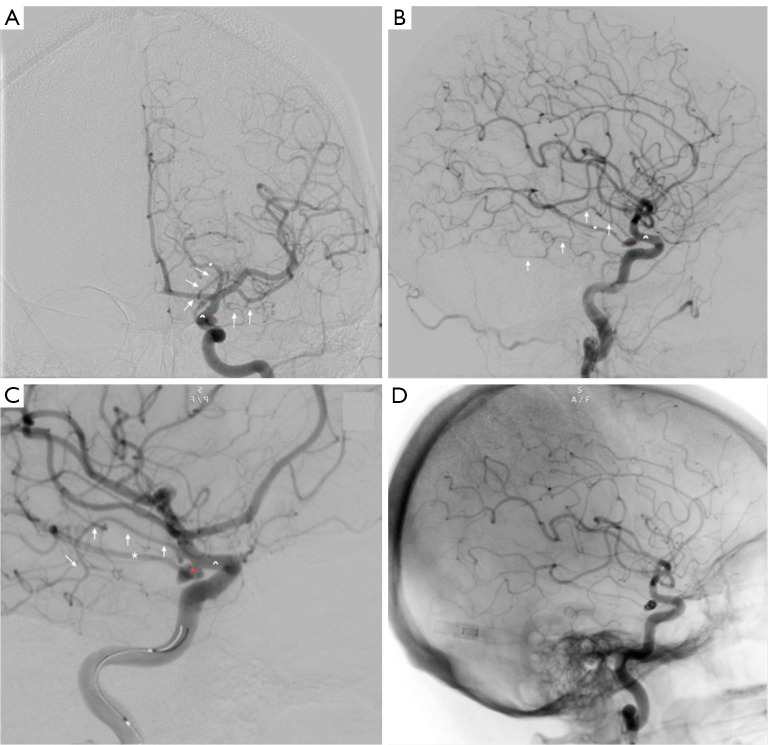

Telencephalic variant of the anterior choroidal artery: clinical significance and management considerations.

脉络膜前动脉远端变异:临床意义和治疗考虑。